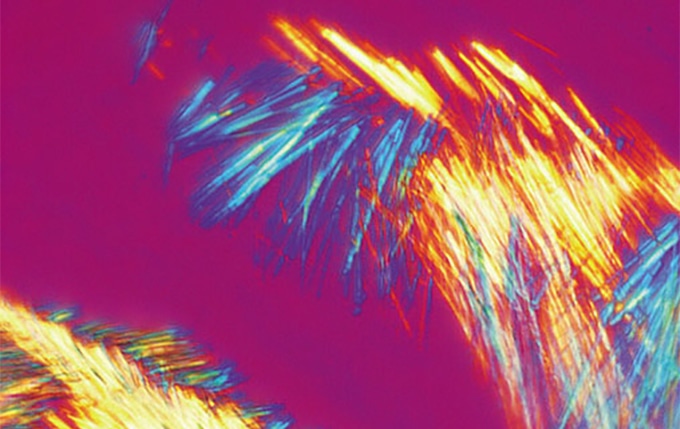

Straightforward Gout Inspection

The microscope can very easily and quickly be adapted for use in the detection of gout, since the analyzer inserts directly into the nosepiece. For routine gout screening, a rotating stage can be mounted instead of the standard mechanical stage.